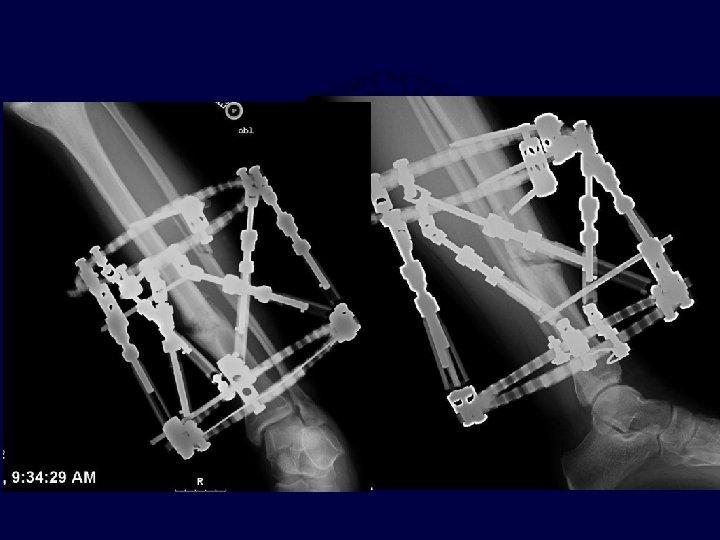

Open Tibia Fracture with Soft Tissue Deficits Appropriate pin placement and construct needed to control varus

Open Tibia Fractures. I&D, Flexible Nailing